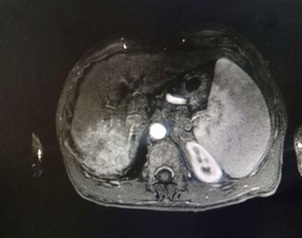

Figure 4: Antrum biopsy of the patient under gastroscopy for pathological examination of fruit (hematoxylin-eosin (HE) staining, ×100).

The patient, a 55-year-old male, was admitted to the hospital on March 11, 2021 due to “upper abdominal distension, pain and discomfort for more than 1 year, and recurrence for more than 2 months”. More than 1 year ago, the patient had no obvious inducement of upper abdominal distension, pain and discomfort, no acid reflux, heartburn, no nausea, vomiting, no hemesis, melena, no chest pain, chest tightness and other discomfort, no care, no diagnosis and treatment. Before 2 months, the patient’s symptoms were aggravated again, and the symptoms continued to be not relieved, so the emergency department was admitted to our hospital as “abdominal distension cause check”. Previous healthy, smoking and drinking history, no similar patients in the family. Improve relevant examinations after admission, such as: Infectious disease screening: hepatitis B surface antigen (gold standard method) positive (+), HBVDNA: 3.89 x 106 IU/ml, TAP: 128.03 um², liver function:TP: 50.23 g/L ALB: 27.8 g/L, TBIL: 34.8 g/L, DBIL: 15.00 g/L, IBIL: 19.8 g/L, ALT: 27 g/L, AST: 51 g/L, PCHE: 1879 g/L, AFP: 203.8 ng/ml, Color Doppler ultrasonography of chest and abdomen showed that liver cirrhosis was possible, portal vein velocity decreased, liver disease gallbladder, splenomegaly and splenic vein dilation. 256 row chest and upper abdomen CT (plain scan + enhanced): 1. Ground glass shadow of left lung, follow-up and reexamination are recommended; 2. Liver cirrhosis, splenomegaly, esophagogastric fundus and splenic collateral circulation; The abnormal enhancement focus in the right lobe of the liver, considering the high possibility of liver cancer, the remaining small nodule like enhancement in the liver, considering intrahepatic metastasis (Figure 1). 3. Gastric antrum space occupying, considering malignancy, please combine clinical and pathological findings. 3.0 Mr upper abdomen (plain scan + enhancement): 1. Liver cirrhosis with regenerative nodules, splenomegaly, portal hypertension, ascites and collateral circulation; 2. Abnormal signal of right posterior lobe of liver (Figure 2). Considering malignancy, please combine clinical and AFP examination. Gastroscopy showed: 1. Esophageal gastric fundus varices (severe); 2. Gastric antrum space occupying: Ca? (Figure 3); Gastric antrum pathology (HE staining Figure 4) results: (gastric antrum) adenocarcinoma. Liver puncture pathology (immunohistochemical (Figure 5) diagnosis: (liver puncture) combined with immunohistochemical results, it is consistent with hepatocellular carcinoma. Immunohistochemistry: CerbB2 (0), CK (+), HEPA (partial +), glypican (+), CD (small amount +), CD34 (blood sinus +), CK7 (-), CK8 (+), CK19 (-), CDX2 (-), Ki67 (50% +), GS (+), CK20 (-). Physical examination: Body temperature was 37OC, pulse was 78 beats/ min, respiration was 20 beats/min, blood pressure was 120/70 MHg, skin and mucosa of the whole body were mildly yellow, no rash, bleeding spots, liver palm or spider nevus, superficial lymph nodes were not touched and enlarged, and no obvious abnormalities were found in head, neck, heart and lungs during physical examination. Abdominal distention, soft abdomen, no obvious tenderness, rebound pain and muscle tension in the abdomen, liver, spleen and ribs are not touched, negative mobility dullness, bowel sounds are normal. The patient refused interventional therapy, asked for oral chemotherapy and was discharged after her symptoms improved.